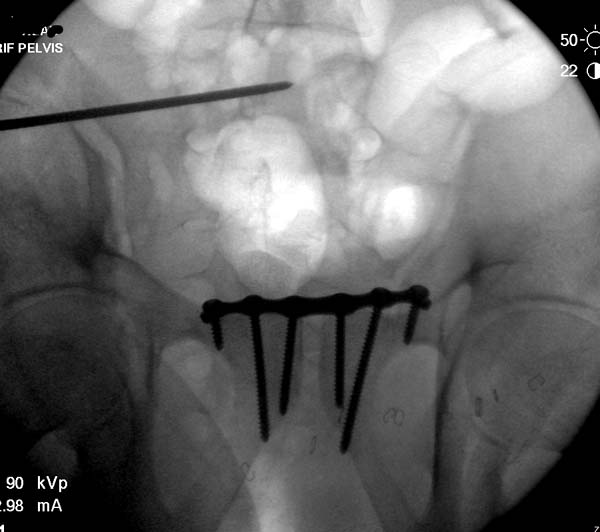

Большое спасибо всем Вам за помощь! Вчера прооперировали пациентку. Выполнили закрытую репозицию левой половины таза на тракционном столе под контролем ЭОП, закрытая фиксация левого КПС двумя каннулированными винтами. Учитывая удовлетворительное стояние отломков лонной и седалищной костей справа, а так же удовлетворительную ширину лона передние отделы стабилизировали системой ЦИТО

Послеоперационные КТ прилагаются

Винты введены в S1

Вроде бы все удалось. хорошо, что фрагмент (как выяснилось из КТ оказался небольшим), но для оценки лучше выкладывать рентген в стандартных проекциях